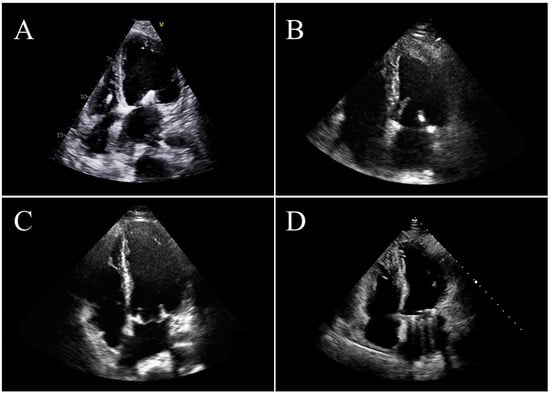

Figure 2.

Four patients after mitral valve intervention: (A) transcatheter edge-to-edge repair; (B) surgical valve repair; (C) surgical valve replacement with a biological heart valve; (D) surgical valve replacement with a mechanical heart valve.